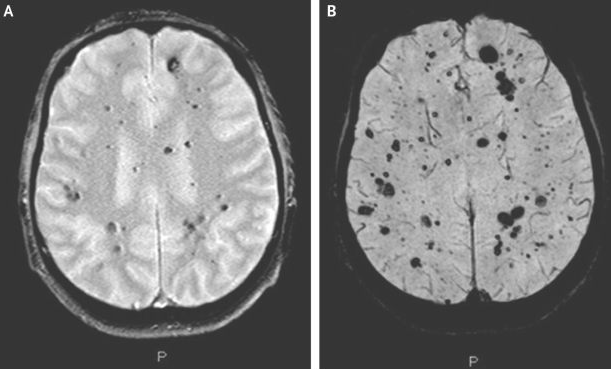

病毒进入人体后,脑内正常蛋白质形态遭到改变,导致大量神经元死亡,形成脑部海绵状空洞和半透明样色素变性,从而引起智力障碍、记忆力下降、视力障碍、运动协调能力减退等症状。

海绵状脑病